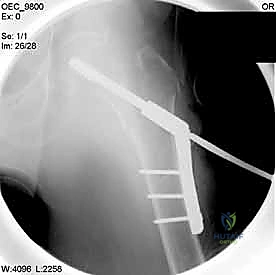

| وجه المقارنة | الشريحة والمسمار المنزلق (DHS - Dynamic Hip Screw) | المسمار النخاعي القريب (PFN - Proximal Femoral Nail) |

| آلية العمل | شريحة معدنية تُثبت على السطح الخارجي للعظم مع مسمار كبير يخترق عنق الفخذ. | مسمار من التيتانيوم يُدخل داخل التجويف النخاعي للعظم (من الأعلى) مع مسامير عرضية للتثبيت. |

| نوع الكسور المناسبة | الكسور المستقرة (Stable Fractures) ذات التفتت البسيط. | الكسور غير المستقرة (Unstable)، المفتتة بشدة، أو التي تمتد لأسفل العظم. |

| الشق الجراحي | شق جراحي جانبي أطول نسبياً (حوالي 10-15 سم). | جراحة طفيفة التوغل، شقوق صغيرة جداً (Minimally Invasive). |

| الميكانيكا الحيوية | يوفر ضغطاً ديناميكياً ممتازاً على موقع الكسر أثناء المشي. | يوفر دعماً ميكانيكياً أقوى لأنه يقع في مركز ثقل العظم (محور تحمل الوزن). |

| فقدان الدم | أكثر نسبياً مقارنة بالمسمار النخاعي. | أقل بكثير. |

| سرعة التعافي | ممتازة، ولكن قد تتطلب حذراً أكبر في الكسور غير المستقرة. | أسرع، ويسمح بتحميل الوزن في وقت أبكر في الحالات المعقدة. |

4. إدخال السلك الدليلي (Guide Wire)

يتم إدخال سلك معدني رفيع جداً عبر العظم باتجاه رأس الفخذ تحت توجيه الأشعة المستمر. هذا السلك يعمل كمسار دقيق سيتبعه المسمار النهائي. يجب أن يكون السلك في الموضع الهندسي المثالي لتجنب اختراق مفصل الورك.

5. الحفر وتثبيت الغرسة (Reaming and Implantation)

يتم استخدام أداة حفر مجوفة تمر فوق السلك الدليلي لتوسيع مسار في العظم. بعد ذلك، يتم إدخال المسمار الرئيسي القوي (سواء المسمار المنزلق أو المسمار النخاعي).

6. التثبيت النهائي (Locking)

لضمان عدم تحرك الغرسة، يتم تثبيتها بمسامير إضافية أصغر في جسم عظم الفخذ. هذه المنظومة الميكانيكية توفر ثباتاً استثنائياً يسمح للمريض بتحريك ساقه فور استيقاظه من التخدير.

مجموعة من الصور الإضافية التي توضح مراحل دقيقة من العمل الجراحي المعقد الذي يجريه الأستاذ الدكتور محمد هطيف لضمان أعلى درجات الدقة الميكانيكية الحيوية: